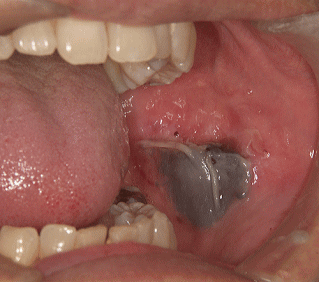

また上下の歯列の咬み合わせが適正なオーバージェット(庇(ひさし)のふかさ)がない場合(バッドジョイントbutt joint:二つの面が毛抜きのように面と面で接触するために誤咬しやすい)も、頬がうまく逃げないために噛みやすく、ひどい場合は血腫を形成することがあります。

血腫を形成した場合、ふつうはそのまま放置しても良好な経過を辿りますが、必ず誤咬の原因を取り除くことが大切です。